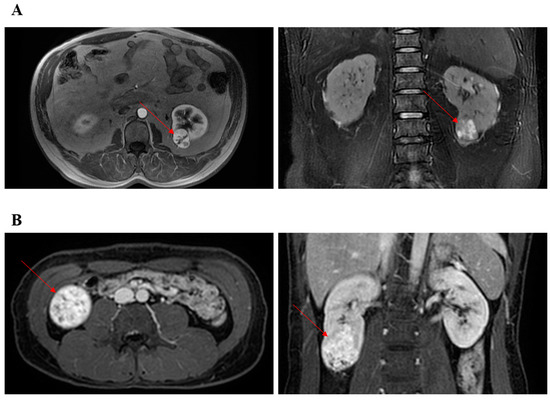

With the approval of our hospital, we performed retrospective patient screening in our former established database. Only patients undergoing TRPN or RRPN between 2013 and 2016 with completely lower pole renal masses were analyzed in the present study (Supplementary Figure S1). The decision of TRPN or RRPN was made by the skilled surgeons. A “skilled surgeon” was strictly defined as a surgeon who has completed more than 300 cases of laparoscopic PN and more than 100 cases of RPN. Therefore, all surgeons had been through the learning curve of TRPN and RRPN. Based on preoperative CT or MRI, two researchers separately screened kidney masses using the R.E.N.A.L. scoring system. Complete lower pole renal tumors were defined as tumors that received 1 point for the “L” element of the R.E.N.A.L. and were located at lower pole of kidney. Figure 1 presented two typical cases undergoing TRPN and RRPN, respectively. The criteria for discharge were no significant bleeding findings, removal of drains, and basic resumption of self-care.

Figure 1. Representative images of CT or MRI. Red arrow points to renal tumor. (A) The patient underwent retroperitoneal robotic partial nephrectomy. (B) The patient underwent transperitoneal robotic partial nephrectomy.